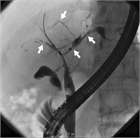

1. PSCとIgG4関連硬化性胆管炎との鑑別診断のためにERCPなどの直接胆管造影を行うことが推奨される(推奨度2、OJ)

1. PSCの診断のためにMRCPを行うことは強く推奨される(推奨度1、RSJG)